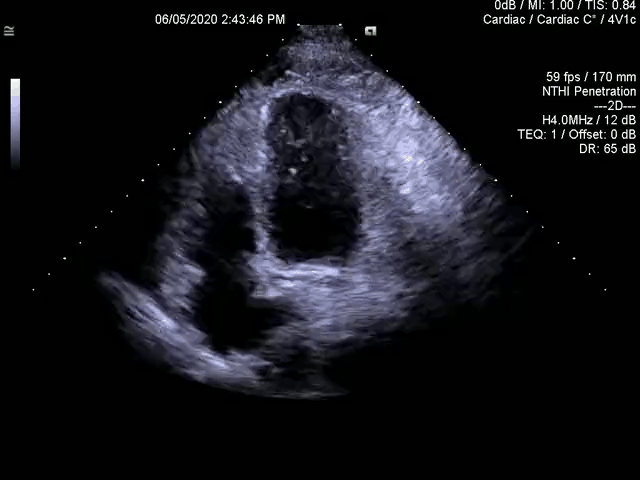

一例晕厥患者,超声心动图发现左心房内占位,手术摘除,术后病理证实粘液瘤